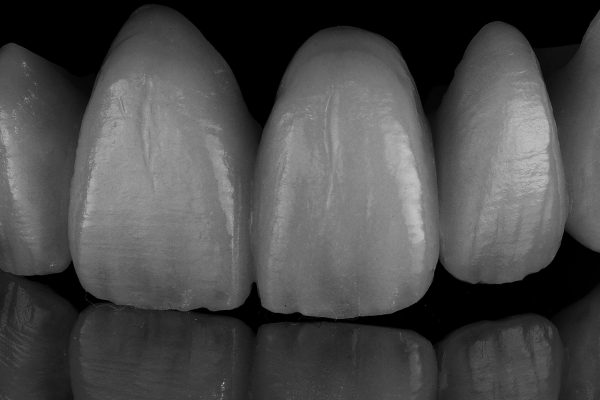

The BioCeramiche, realized by us, are protected in their recipe and manufacturing process by THREE INTERNATIONAL PATTENTS of our exclusive property (n° 01315293 – 01307082 – 01343575 Submitted to the Ufficio Italiano Brevetti) .

We are therefore able to create Unique, Personalized, and Original products